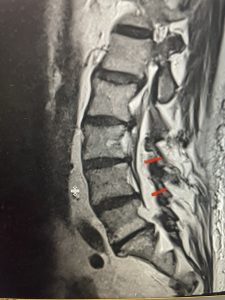

The next patient is a 71 year-old male with a two-year history of low back pain and lower extremity pain, numbness and weakness. His left leg was worse than the right. He had had five epidurals with no improvement. He also had tried physical therapy and medicines but nothing helped. He also felt that over the last three weeks he had gotten worse. He also had recently had some decreased sensation of bladder fullness and difficulty with bowel movements. MRI revealed a very tight L2-5 stenosis with an extruded L3-4 disc fragment (Fig 3).

(Figs 3a) Sagittal (a) and Axial (b) T2-weighted lumbar MRI demonstrating severe spinal stenosis L2-5 (arrow)and extruded disc at L3-4 on axial image (arrow)

He had concentric severe stenosis with severe compression of the lateral recess and foramen at L3-4 secondary to the superimposed disc herniation. The fact that he had gotten worse with subtle cauda equina features with an extremely tight canal, he underwent a decompressive laminectomy. We also augmented his laminectomy with an in situ fusion from L3-5 as he was relatively young, with more time to reform arthritis, and had been unstable enough to extrude a disc fragment. By placing “bone dust” or bone material along the sides of the spine, specifically laying it across the transverse processes after they have been drilled to bleeding bone, you provide an environment where bone formation is induced to connect the segments, stabilize them, and thereby reduce the signal to make more arthritis as that signal is still present despite the laminectomy. What was interesting was that we encountered a large extruded disk fragment that was significantly contributing to his compression which is often not found in patients in this age bracket. Post operatively he had much improvement of leg pain.